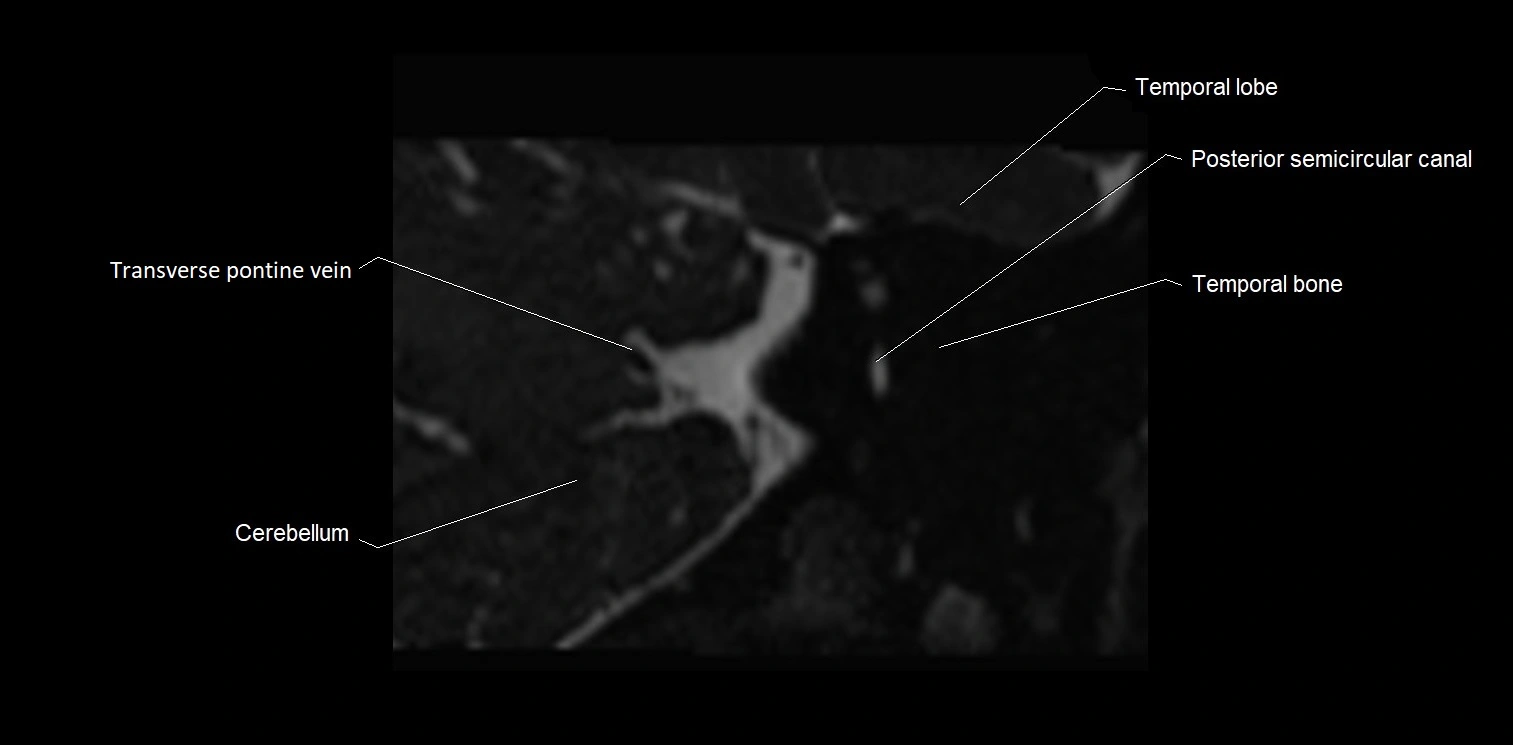

MRI Appearance

• The abducens nerve is a small, thin, linear structure

• Best visualized on high-resolution T2-weighted 3D MRI sequences (e.g., FIESTA or CISS)

• Seen as a hypointense (dark) line running from the brainstem at the pontomedullary junction, traversing the prepontine cistern, and entering Dorello’s canal under the petrosphenoidal ligament, then into the cavernous sinus, and finally the orbit

• May be challenging to visualize in standard MRI due to its small size

• Pathology may be inferred by absence, displacement, or enhancement of the nerve

MRI images

image